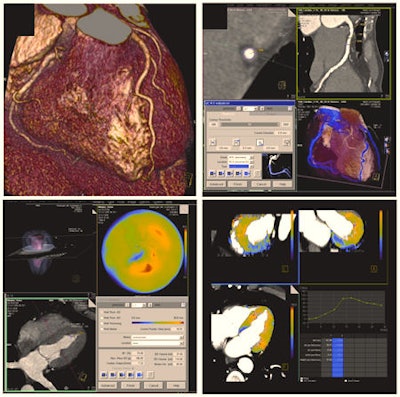

Today, contrast-enhanced cardiac CT is mainly used to display cardiac and coronary morphology in motionless images. Results can be displayed through volume-rendering techniques (top left) or dedicated software can be used for a detailed analysis of the coronary arteries and potential coronary artery stenosis -- e.g., using curved multiplanar reformats (top right). However, cardiac CT can also analyze cardiac function (global functional parameters and also regional wall motion, displayed in color maps, bottom left). Recent developments and research are focusing on the assessment of myocardial perfusion -- e.g., using dynamic, time-resolved acquisition modes. This way, blood flow through the myocardium can be displayed in color maps or in time-density curves, potentially allowing assessment of the hemodynamic significance of a given coronary artery stenosis (bottom right).In addition, researchers have started to use CT to differentiate between types of coronary plaques. Plaques in the vessel wall not only consist of calcium, but also other tissues such as fibrotic, fibro-fatty and necrotic core tissues, all of which may have a predictive value for the patient. "Today, we would hardly make a clinical decision based on CT plaque imaging alone, but it is one of the important topics in cardiac CT research," Nikolaou said.